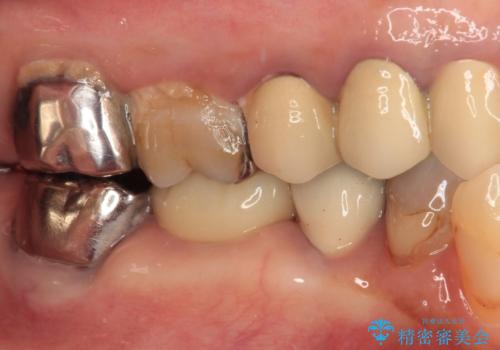

銀歯を外したところ、非常に大きなむし歯が認められましたが、神経組織には及んでおらず、速やかにオールセラミッククラウンによる補綴治療を行いました。